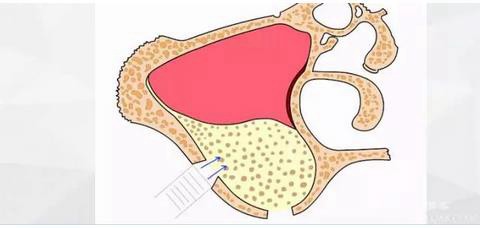

以前我也發(fā)表過兩篇類似的博客,里面闡述了“改良式外提升”的概念(原創(chuàng):梁光強):在沒有開窗之前就已經(jīng)將頰側上頜竇膜和上頜竇骨壁分離,從而使接下來的開窗不會與上頜竇膜有接觸,是一種安全、快捷、方便的側壁開窗技術。

現(xiàn)在為大家展示改良式外提升工具盒工作原理:

首先使用開孔鉆刺穿上頜竇頰側骨壁。

水壓將頰側上頜竇膜剝離。

擴大窗口,此時因為上頜竇膜已經(jīng)與骨壁分離,所以打磨時不會損傷到膜。